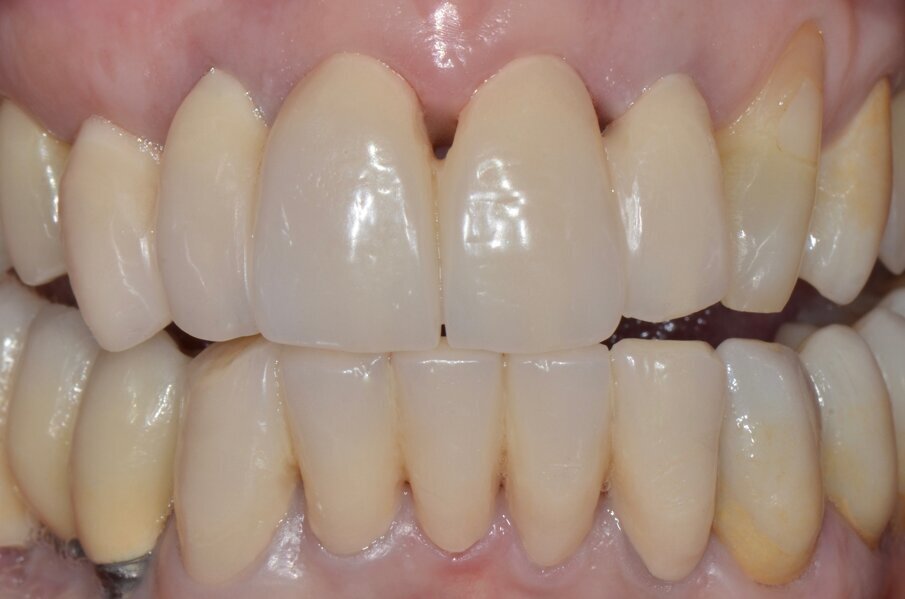

Riguardo al comparto intraorale, dalle radiografie diagnostiche e dall’esame parodontale e occlusale sono emersi aspetti che meritavano una correzione anche nei settori posteriori, ma la paziente ha deciso di effettuare inizialmente il trattamento dei soli gruppi frontali superiore e inferiore demandando a un momento successivo le problematiche dei quadranti posteriori (Figg. 2-6). Nel gruppo frontale superiore si possono notare recessioni gengivali sugli incisivi centrali, che sono anche molto ruotati, e sul canino di sinistra; corone in metallo-ceramica sugli incisivi laterali con esposizione del bordino metallico e una corona in ceramica metal-free sul canino di destra. Inoltre è molto evidente lo squilibrio delle parabole gengivali tra i due canini, per cui per ristabilire un’estetica ottimale sarà necessario anche interessare i tessuti molli eseguendo una chirurgia resettiva sul canino di destra e, al contrario, un lembo a posizionamento coronale sul canino di sinistra (Fig. 7).

Da un punto di vista protesico verranno eseguite corone singole in zirconia stratificata sugli elementi 13-12-11-21-22 e una faccetta in disilicato di litio sul 23. A causa della notevole rotazione dei due incisivi centrali in fase di ceratura abbiamo optato per due corone complete anziché due faccette per una migliore distribuzione degli spazi protesici dei quattro incisivi (Fig. 8). Il gruppo frontale inferiore invece verrà protesizzato con corone in zirconia stratificata sugli elementi 32-31-41-42-43 splintate per compensare una mobilità di grado 1 dei quattro incisivi.